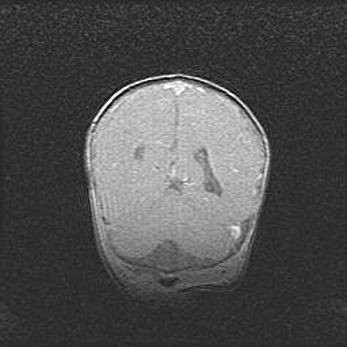

Мальформация Денди-Уокера. Киста задней черепной ямки.

Агенезия мозолистого тела.

Возраст: 2,5 месяца

Вес: 2420 г

Пол: женский

Окружность головы: 37 см

Срок гестации: 32 недели

Мальформация Денди—Уокера — редкий вид патологии ЦНС, представляющий собой врожденный порок развития каудального отдела ствола и червя мозжечка, ведущий к неполному раскрытию срединной (Мажанди) и латеральных (Лушка) апертур IV желудочка мозга. Для этогно синдрома характерна триада симптомов: гипотрофия червя мозжечка и/или полушарий мозжечка, кисты задней черепной ямки, гидроцефалия различной степени. В 70% случаев порок сочетается и с другими аномалиями головного мозга, в частности с агенезией мозолистого тела.